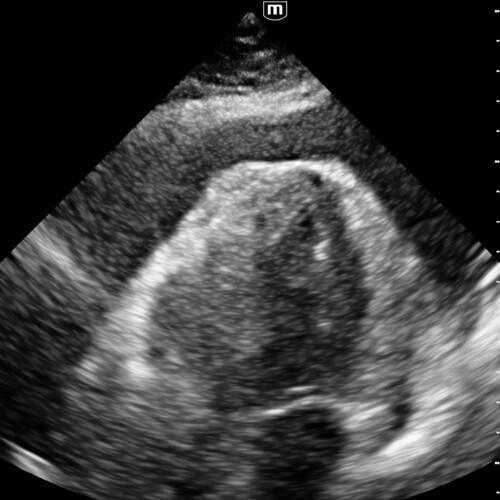

Vue parasternale grand axe

Permet de différencier :

- un épanchement péricardique, entourant tout le cœur,

- d’un épanchement pleural, situé en arrière de l’aorte descendante.

- Idéale pour visualiser le péricarde postérieur et la racine aortique.